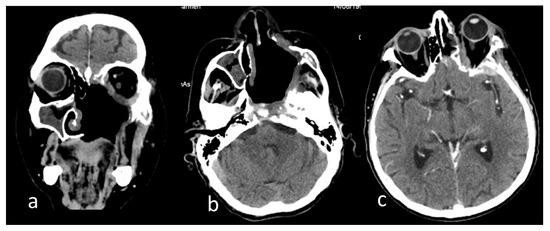

2. Case Report